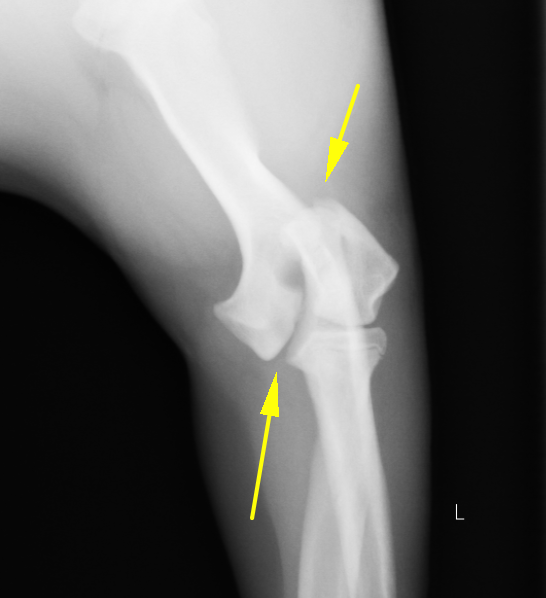

術前のX線画像です。どこが折れているかお分かりでしょうか

骨折部位のアップになります。矢印の部分が骨折断端となります。